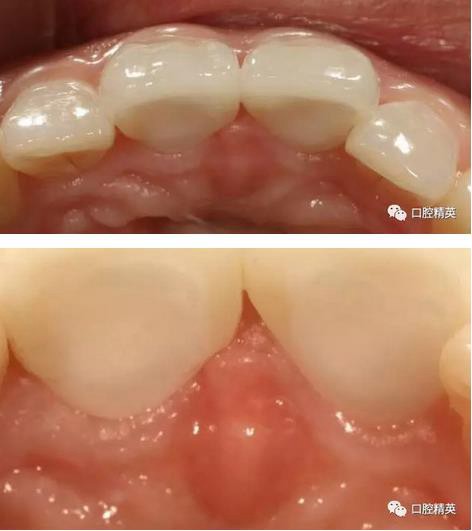

修復體展示

修復體戴入

口內(nèi)正側(cè)位及切端特寫